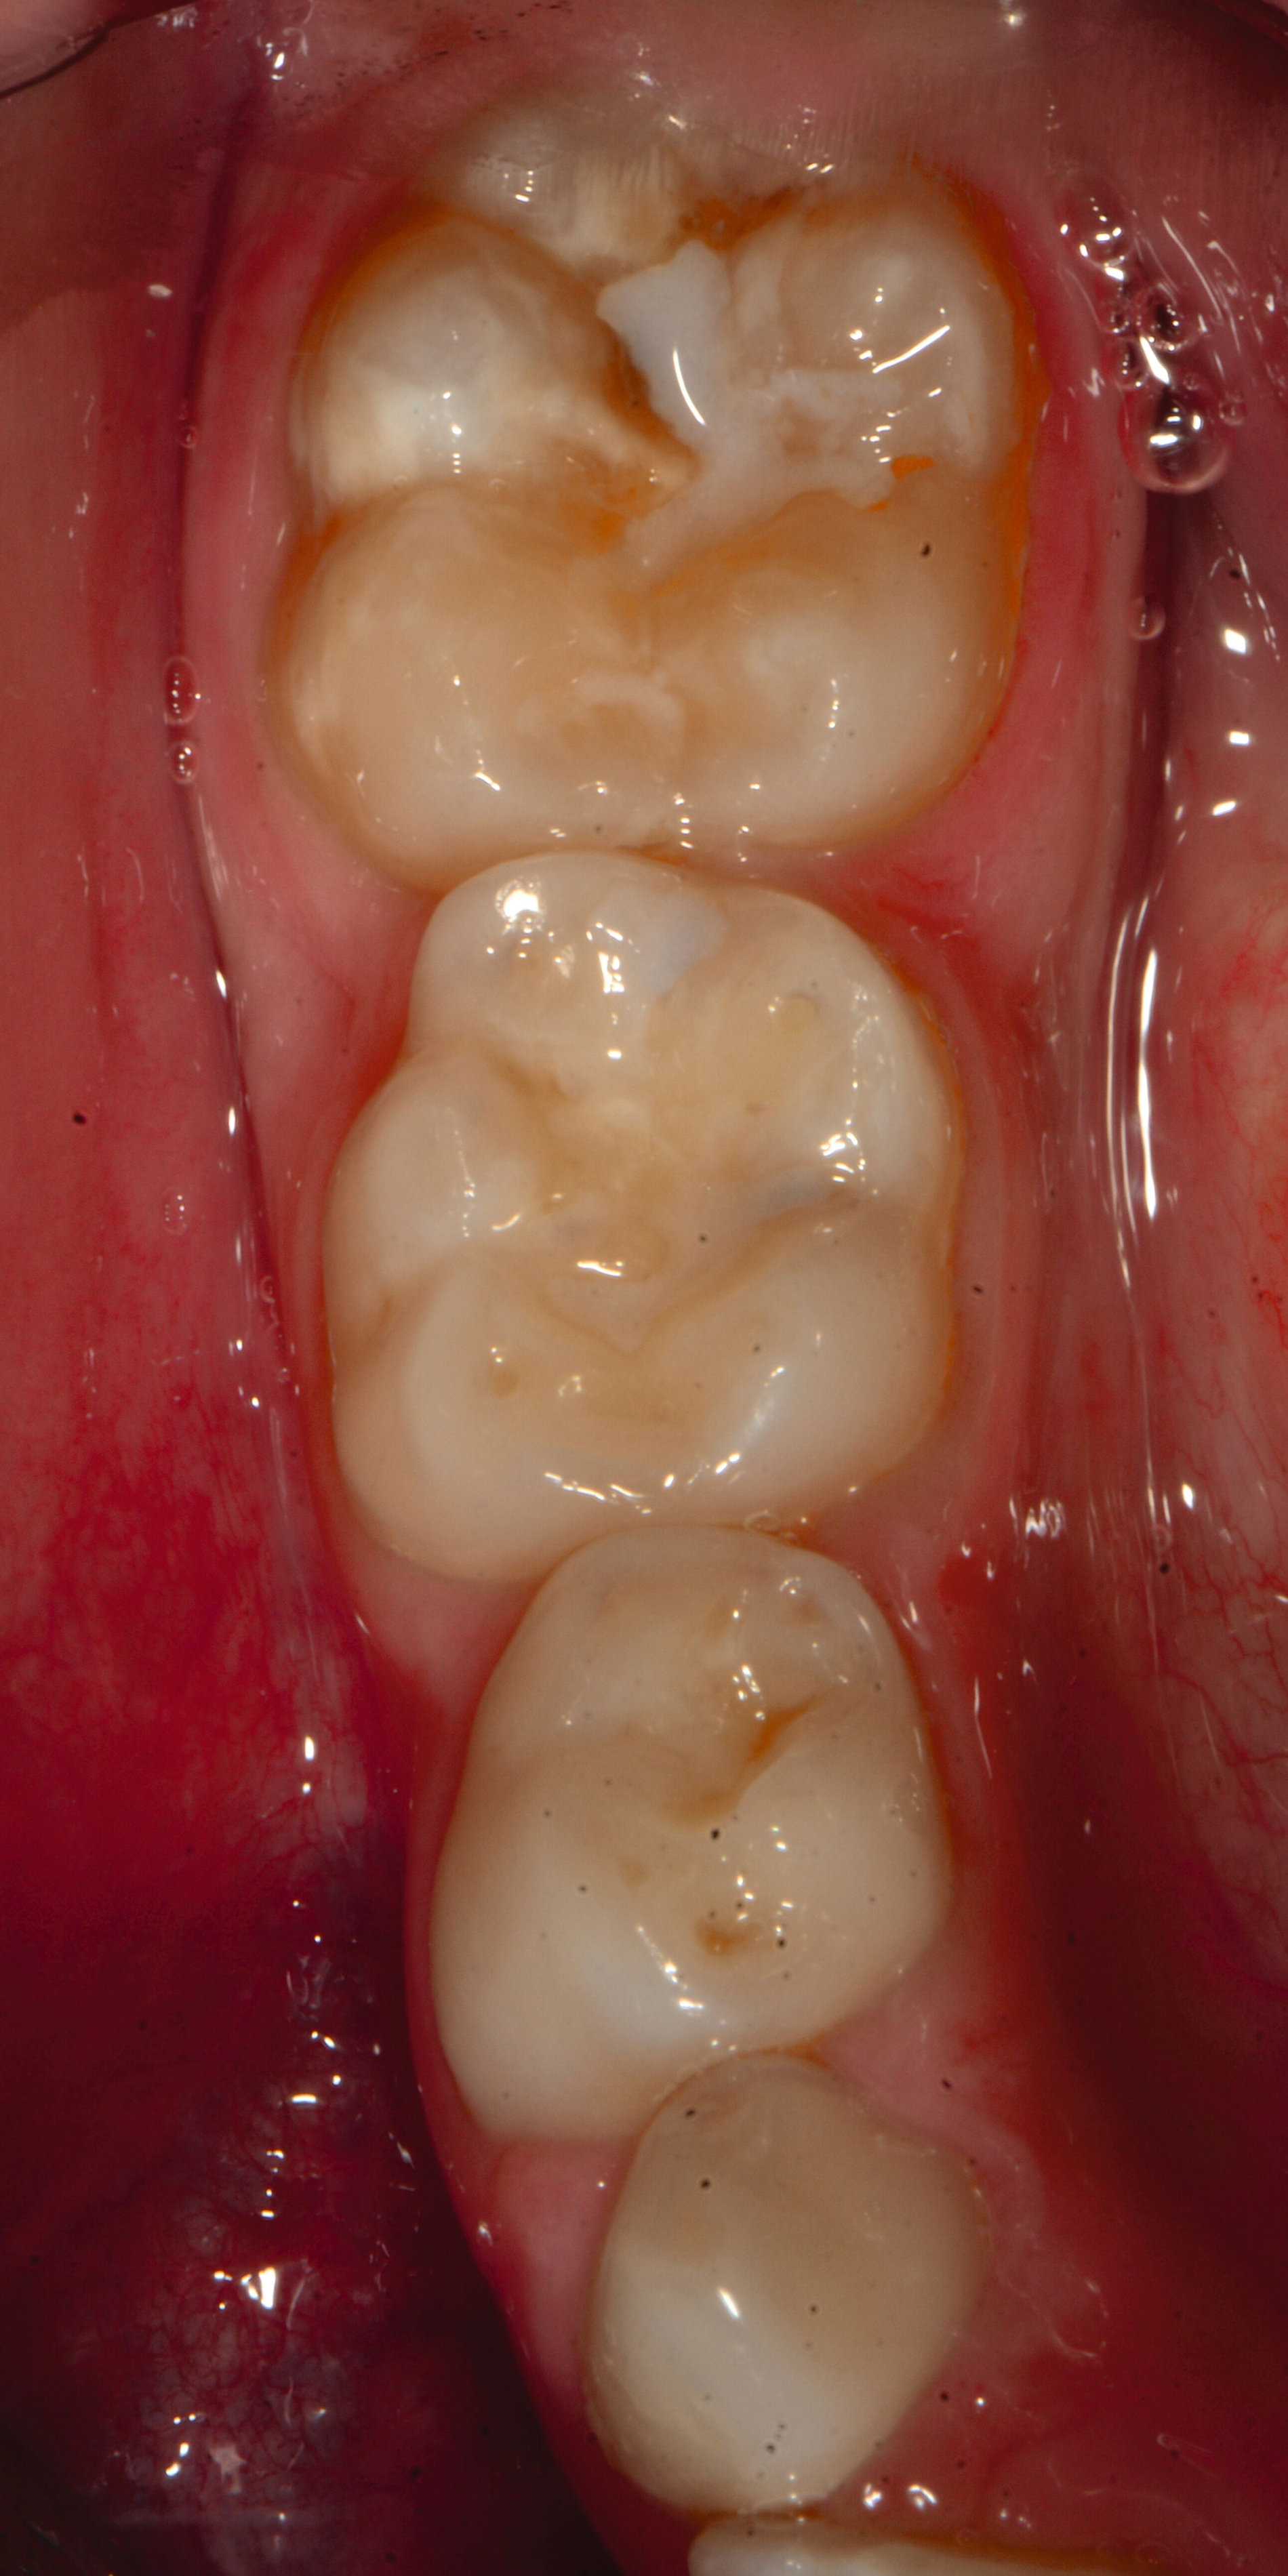

Das klinische Erscheinungsbild an bleibenden Zähnen zeigt typischerweise weißlich-gelbe bis gelblich-braune Opazitäten, die zumindest in einigen Bereichen durch eine scharfe Abgrenzung (engl.:„demarcated opacities“) zum gesunden Zahnschmelz charakterisiert sind (Abbildungen 3 und 4). Die abgegrenzten Hypomineralisationen befinden sich mehrheitlich im Bereich der inzisalen Kronenhälfte unabhängig von dem Auftreten an Front- oder Seitenzähnen. Die Ausprägung am Zahn kann dabei auf einzelne Areale oder Höcker begrenzt sein.

Bei einer schwerwiegenderen Ausprägung sind Zahnflächen vollständig betroffen, mitunter alle Zahnflächen an einem Zahn. Die Verteilung in der Dentition beziehungsweise an den Indexzähnen ist gleichermaßen variabel und betrifft nicht nur die Defektgröße, sondern auch die Farbe und Festigkeit. Was die Festigkeit betrifft, gilt als die Faustregel: Je dunkler die Farbe des Schmelzes, umso weicher beziehungsweise poröser und damit minderwertiger wird dessen Qualität sein. Damit reduziert sich seine kaufunktionelle Belastungsfähigkeit, was insbesondere an ersten bleibenden Molaren von klinischer Relevanz ist.

Für die Dokumentation und Klassifikation der MIH wurden verschiedene Systeme vorgeschlagen. Als historisch und veraltet gilt der (modifizierte) DDE-Index. Demgegenüber haben die Kriterien der EAPD – abgegrenzte Opazitäten (Abbildung 3 und 4), Schmelzeinbrüche (Abbildung 5), atypische Restaurationen (Abbildung 6) – mittlerweile die weiteste Verbreitung gefunden. Diese wurden 2003 erstmals zur Beschreibung der MIH auf empirischer Basis publiziert [Weerheijm et al., 2003] und den Jahren 2010 und 2022 im Rahmen der damaligen MIH-Workshops bestätigt [Lygidakis et al., 2010; 2022].